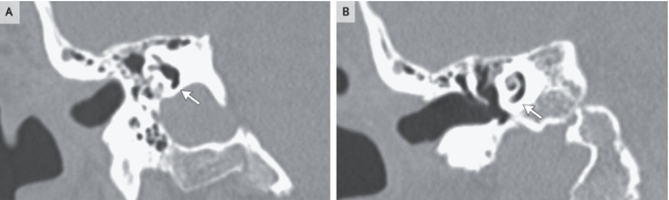

頭部CT画像では後頭部骨折と耳嚢(内耳構造を取り囲む骨)を通じた右側頭部骨折が明らかになり、その結果、迷路内(A)および蝸牛内(B)の空気の異常が生じていた。